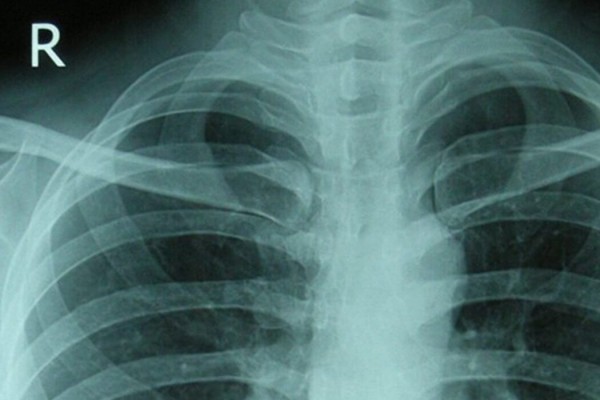

8 ноября отмечается международный день радиологии отмечается. Впервые этот праздник отмечался в 2012 году. Организован он был по совместной инициативе Европейского и Северо-Американского общества радиологов. В число участников празднования Дня радиологии входят специалисты радиодиагносты и радиотерапевты, а также их друзья и близкие родственники.

8 ноября 1895 года впервые открыли рентгеновское излучение, что повлекло за собой образование новой дисциплины – радиологии. Именно в честь этого события и была выбрана ежегодная дата празднования Международного дня радиологии. Основной целью такого праздника является привлечение внимания общества к радиологии и к ее положительным сторонам.

Радиология является одним из медицинских направлений. Изучает она возможности и последствия, которые образовались в результате использования ионизирующих волн, для лечения заболеваний различной степени тяжести. Специалисты данной области борются и с последствиями контактов с радиоактивными волнами.